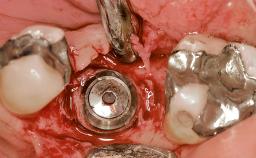

Early Placement of an Implant in a Maxillary Right Central Incisor Site

Bone Augmentation | Horizontal|Simultaneous |

Augmentation Materials | Autogenous chips|Xenogenous|Membrane |

Bone Volume | Deficient horizontally, allowing simultaneous augumentation |